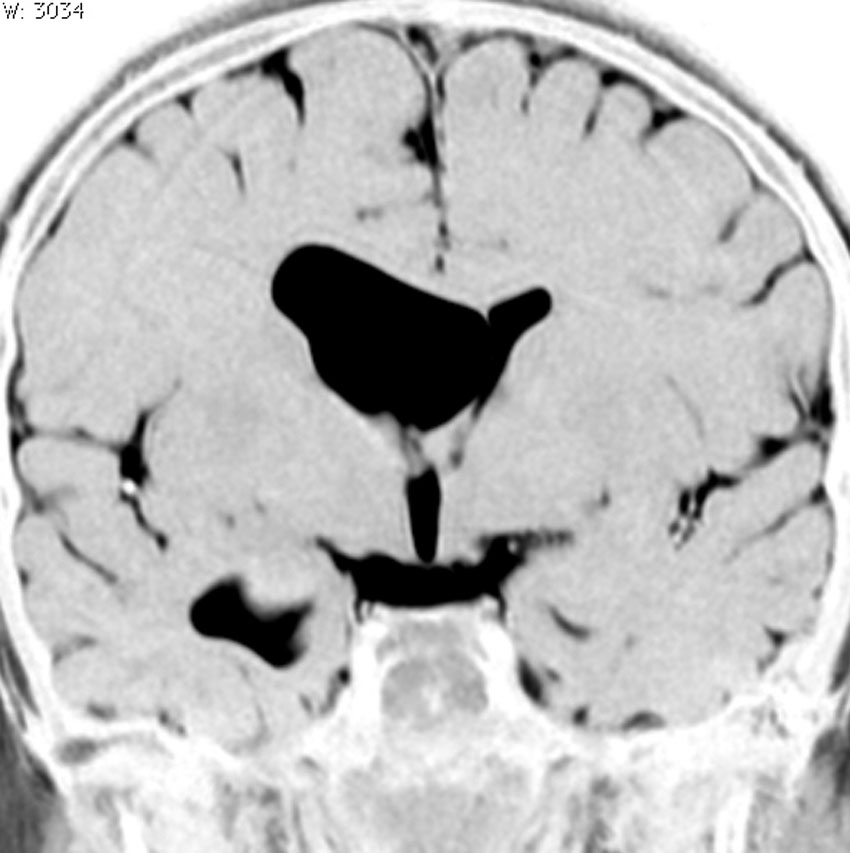

脳室内くも膜のう胞

くも膜のう胞が脳室内にできて,脳室の一部で髄液の流れをさまたげて,部分的な水頭症になることがあります。水頭症になっても停止性水頭症というもので悪化傾向がなければ治療の必要がありません。多くは側頭角というところが拡大するのですが,拡大傾向がはっきりしたら,内視鏡手術でくも膜のう胞の壁を切除します。

これは11歳の子供で偶然発見された右側脳室くも膜のう胞です。無症状で変化しませんからほっておきます。右のモンロー孔に狭窄があるために右側脳室だけの停止性水頭症になっています。